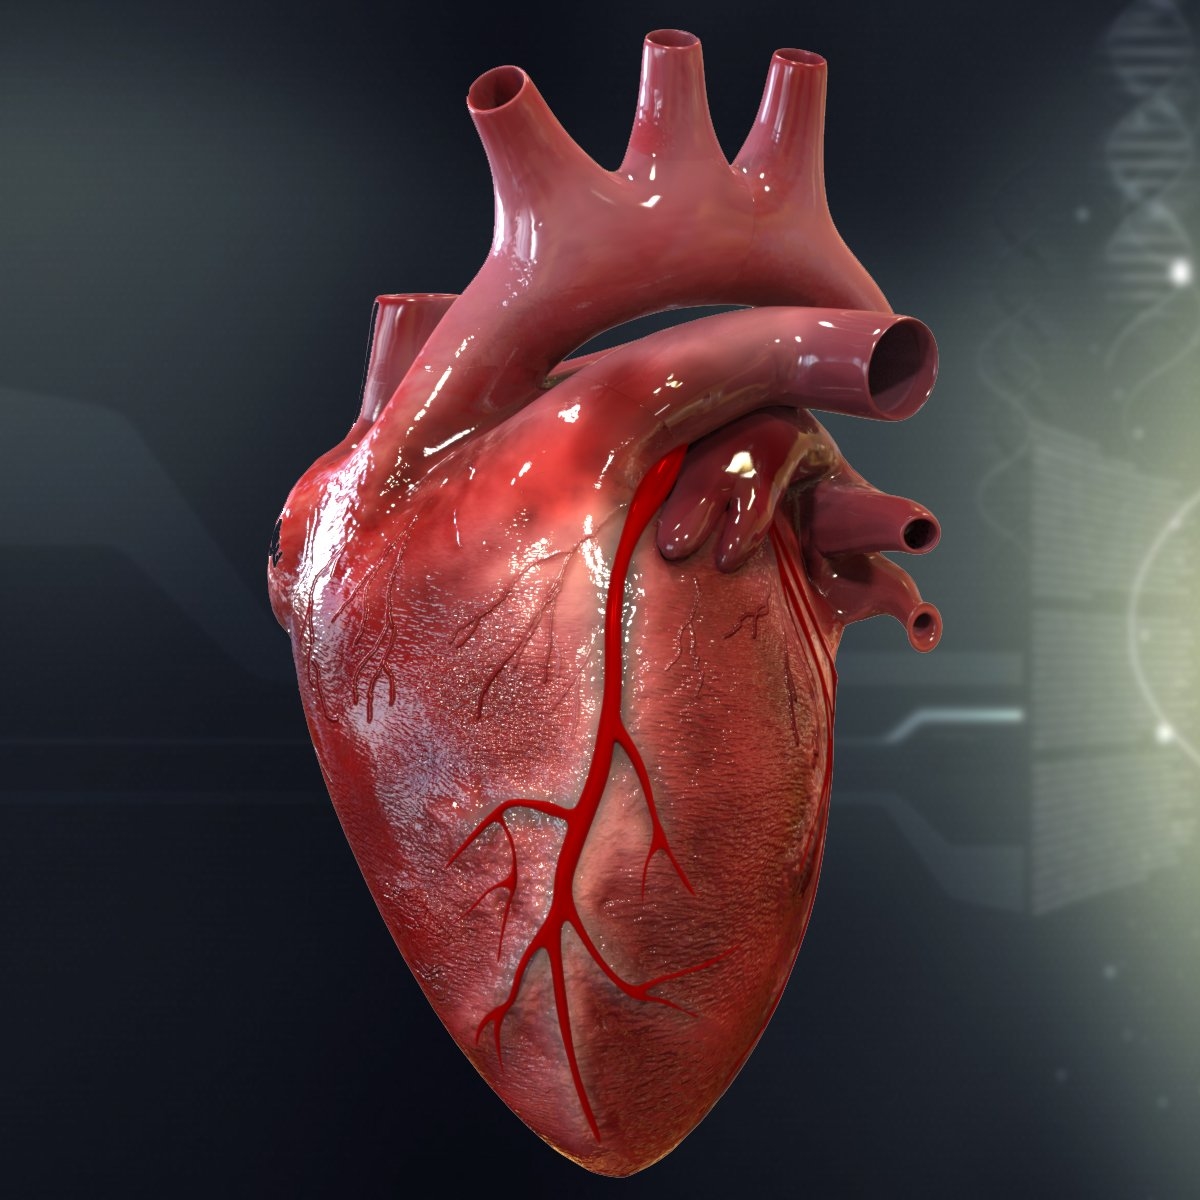

3d human heart  Animated Realistic Human Heart - Medically 3D asset

Animated Realistic Human Heart - Medically 3D asset  Zygote::3D Heart Model | Medically Accurate | Human Anatomy

Zygote::3D Heart Model | Medically Accurate | Human Anatomy  Zygote::Solid 3D Human Heart Model

Zygote::Solid 3D Human Heart Model  3D human heart anatomy model - TurboSquid 1283134

Realistic Human Heart 3D model | CGTrader  anatomy human heart 3d c4d

Image of Human Heart 3D Illustration | Stock Image MXI28575  The human heart by SkarlettFury on DeviantArt | Human heart drawing, Heart drawing, Heart art

Heart Anatomy Human Heart Images Hd 3D - Dreaming Arcadia  Pin on Body Parts Drawings

Heart Diagram Human Heart Images Hd 3D - img-Badr  Real Human Heart Drawing at GetDrawings | Free download